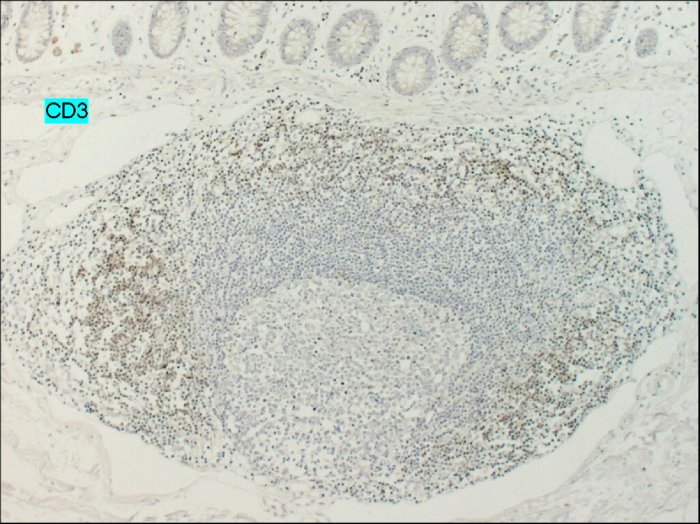

A differenza della forma gastrica, comunque rara, che può associarsi a lesioni ulcerose, questo non si verifica nella forma a localizzazione intestinale. Dal punto di vista istologico i noduli sono costituiti da infiltrato linfoide, composto soprattutto da linfociti B (più raramente linfociti T e plasmacellule) con rare plasmacellule, prominente, confinato alla lamina propria e alla superficie sottomucosa. Nella Figura 3 la reazione positiva per l'anticorpo CD20 dimostra la presenza di linfociti B nell'infiltrato, mentre la negatività dell'anticorpo CD3 conferma che l'infiltrato non è costituito dai linfociti T.